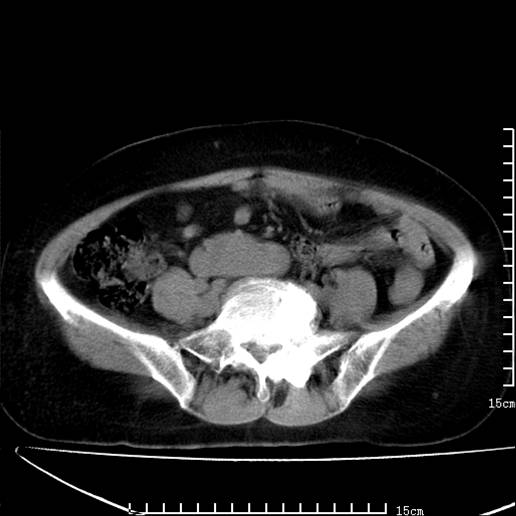

以下是引用pujunzhi在2008-5-30 15:31:00的发言:[br]异位肾—盆腔肾。当看到肾窝无肾脏时,要想到孤立肾和异位肾,异位肾最常见是盆腔肾,偶见胸腔,易误认为肺占位,只要想到就不会漏诊。建议增强扫描。